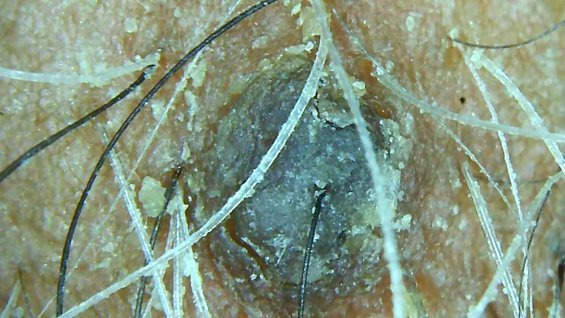

Haircare Transformations Scalp Analysis Scalp Analysis Before After Before After Before After Before After Before After Before After Before After Before After